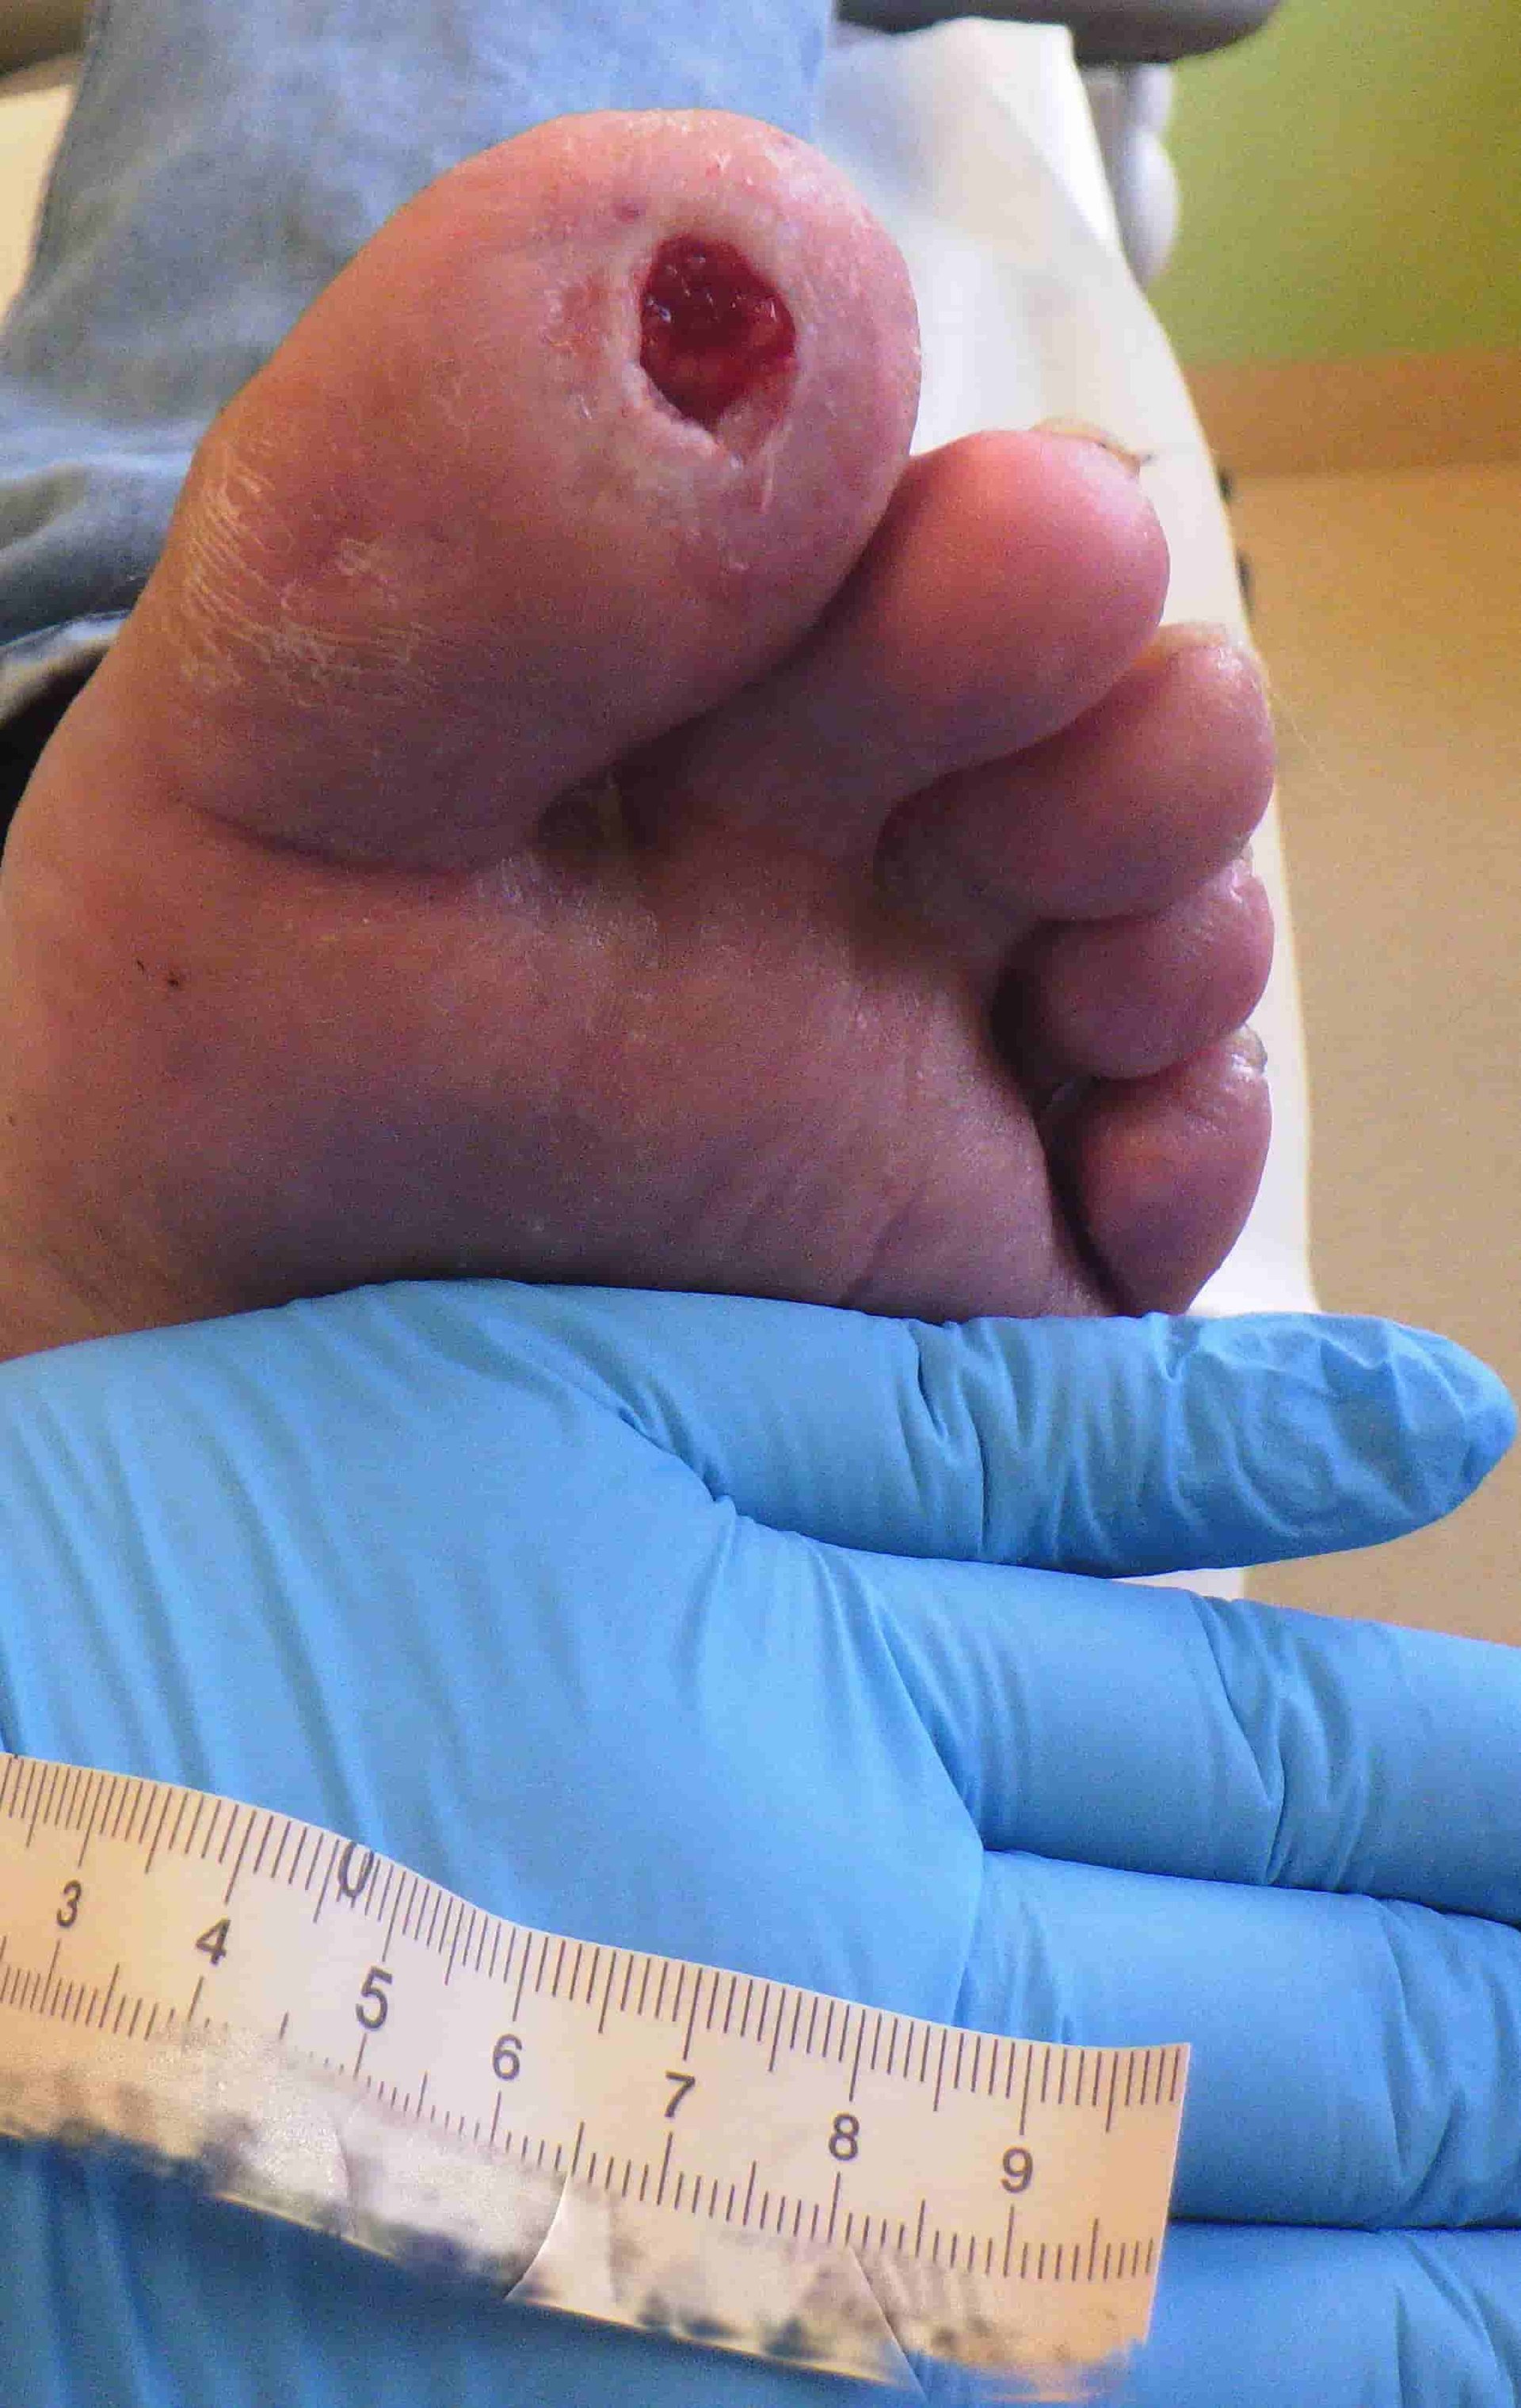

Fallbeispiel: Abszess am Zeh nach Trauma

Ein Aufpralltrauma führte bei diesem Patienten zu einem Hämatom am großen Zeh (D1). Aufgrund einer unzureichenden Wundversorgung entwickelte sich hieraus ein Abszess. Erschwerend kamen der Alkohol- und Tabakkonsum des Patienten sowie eine pAVK hinzu. Wie konnte in diesem Fall eine Amputation vermieden werden? Welche therapeutischen Maßnahmen führten zur Wundheilung? Das lesen Sie in unserem Fallbeispiel.

Nachdem der Patient sich den großen Zeh (D1) gestoßen hatte, erlitt er zu Beginn ein Aufpralltrauma. Die Epidermis an D1 war stark verletzt worden, ein Hämatom hatte sich gebildet. Aufgrund einer unzureichenden Wundversorgung entwickelte sich ein Abszess und mithilfe einer Blutentnahme wurden hohe Entzündungsparameter festgestellt. Nach anfänglichen mechanischen und chirurgischen Debridements entließ sich der Patient selbst frühzeitig aus dem Krankenhaus aus Angst vor einer vom Arzt angeratenen Amputation. Somit konnte eine weitere optimale Sanierung nicht stattfinden.

Nachdem sich der Patient eigenständig aus dem Krankenhaus entlassen hatte, wurde mit der strukturierten Wundversorgung und einer Kausaltherapie begonnen.

Zu Beginn der Versorgung stand die Wundreinigung und somit die Reduzierung der Keimlast im Vordergrund. Da eine pAVK im Stadium I und ein starker Nikotingenuss beim Patienten vorlagen, wurde davon ausgegangen, dass ein Sauerstoffdefizit im Bereich der Zehenkuppen besteht. Aus diesem Grund wurde bei dem Patienten nach der Wundreinigung eine Kaltplasmaanwendung durchgeführt. Durch diese Anwendung werden Bakterien abgetötet und die Sauerstoffsättigung im Bereich der Wunde steigt für eine gewisse Zeit. Dieser Effekt unterstützte die Wundheilung.